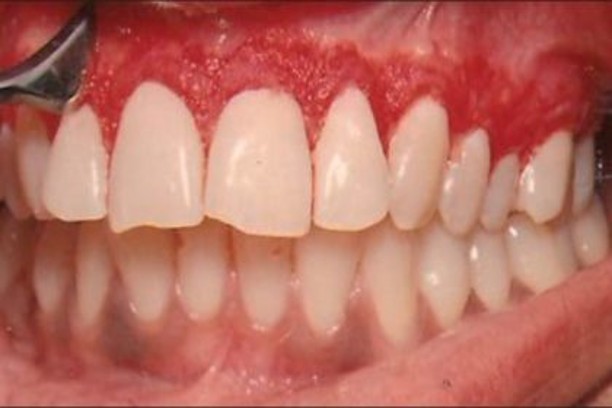

Flap Surgery

Advanced gum surgery to treat periodontal disease and restore gum health.

Gingivectomy

Surgical reshaping of gum tissue for healthier and more aesthetic smiles.

Crown Lengthening

Exposure of more tooth structure for improved restoration and smile appearance.